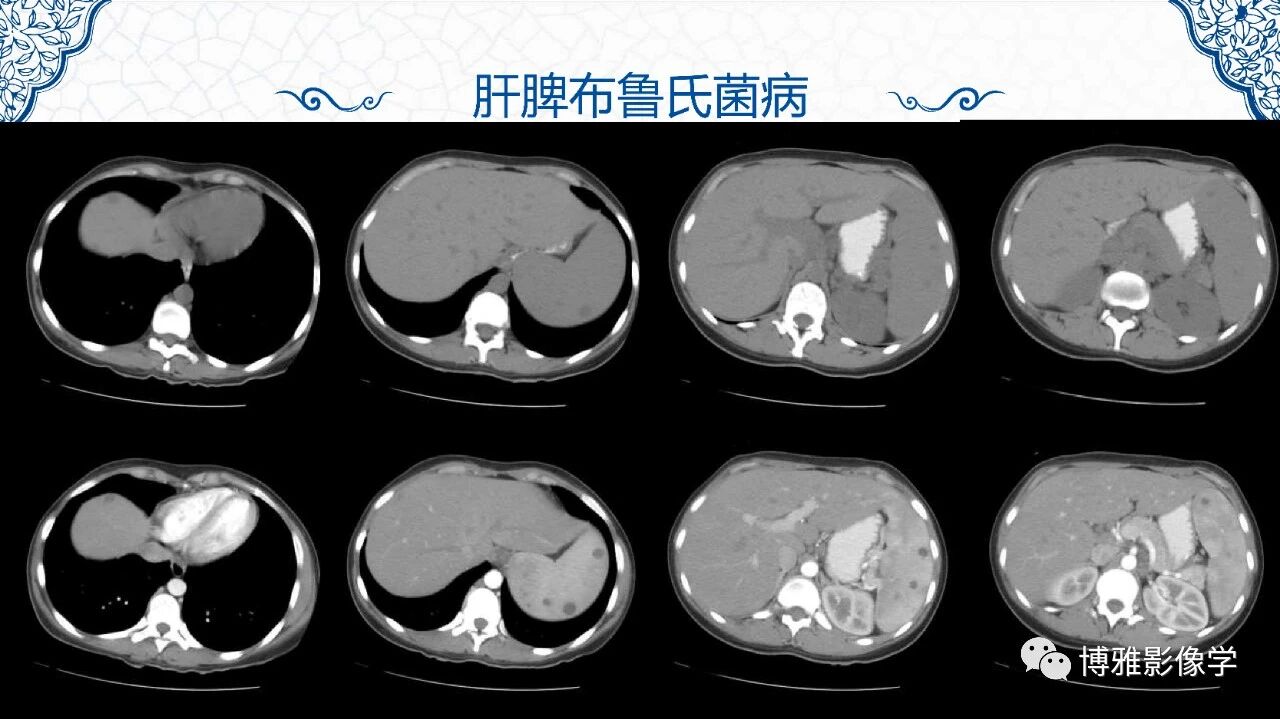

脾脏非肿瘤影像诊断